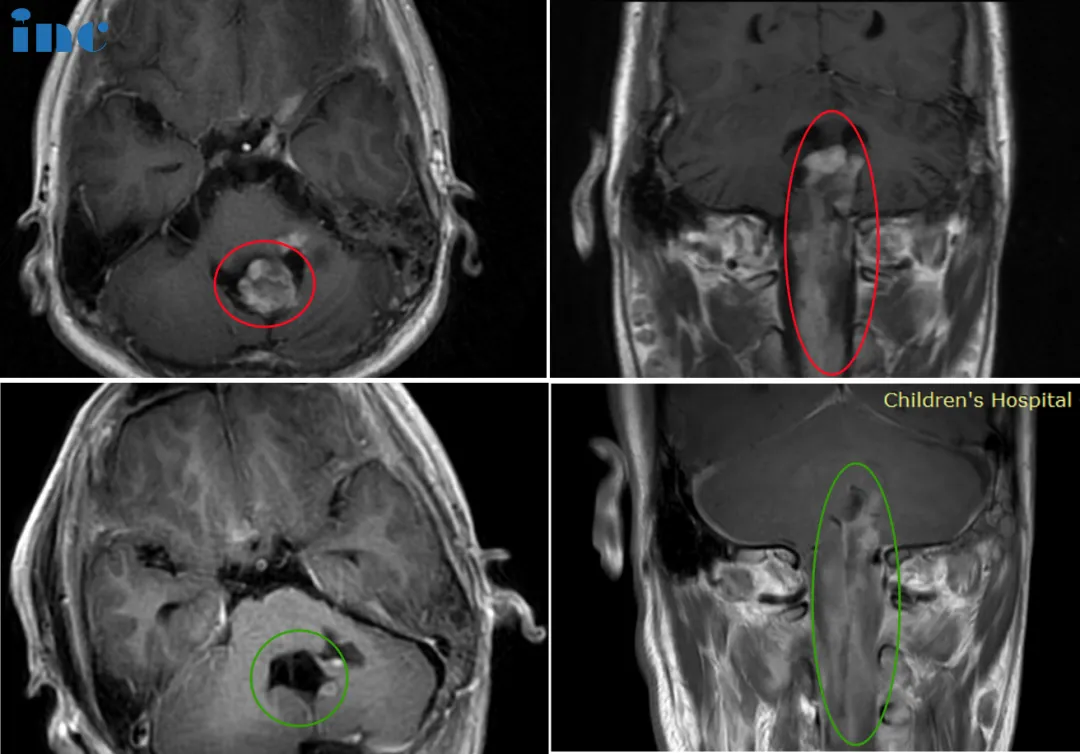

14歲男孩-脊髓髓內(nèi)節(jié)細(xì)胞膠質(zhì)瘤

14歲的睿睿2016年底偶發(fā)左手抓握力弱,2017年初查出神經(jīng)節(jié)細(xì)胞瘤;醫(yī)生表示腫瘤生長(zhǎng)緩慢,無(wú)法全切,還會(huì)復(fù)發(fā),故保守觀察。2021年底,雙側(cè)肢體無(wú)力加重,左側(cè)更明顯。2022年睿睿再次就醫(yī)檢查,腫瘤位于腦干延申至脊髓,腫瘤占位大小33*42*94mm。在國(guó)內(nèi)某醫(yī)院做了一次開(kāi)顱手術(shù),雖仍有不少殘留,但手術(shù)取得完整病理,腫瘤導(dǎo)致的病情有適當(dāng)好轉(zhuǎn),為后續(xù)手術(shù)提供了清晰的思路、爭(zhēng)取了時(shí)間……

▼巴教授術(shù)前術(shù)后影像對(duì)比

巴教授遠(yuǎn)程郵件回復(fù)

“是的,男孩可以接受手術(shù),而且,為了生存,這是他的機(jī)會(huì)。如果不做手術(shù)的話,由于腫瘤的進(jìn)展,盡管已經(jīng)做過(guò)氣管造口術(shù),男孩會(huì)出現(xiàn)很?chē)?yán)重的吸入性肺炎和逐漸惡化的四肢麻痹。因此,應(yīng)該給他生存的機(jī)會(huì),幸運(yùn)的話臨床癥狀在一定程度上會(huì)有好轉(zhuǎn),尤其腫瘤不是惡性的”

在手術(shù)后會(huì)殘留一些較小的腫瘤部分。對(duì)于此,靶向化療是治療選擇,也許也會(huì)有質(zhì)子治療的指征,但這是比較晚的時(shí)候。對(duì)于這種節(jié)神經(jīng)膠質(zhì)瘤的病人來(lái)講,都存在復(fù)發(fā)的風(fēng)險(xiǎn)。但另一方面,隨著時(shí)間的推移,腫瘤的侵襲性將明顯地降低,腫瘤再生長(zhǎng)的風(fēng)險(xiǎn)也會(huì)低很多。甚至后期再次手術(shù)也是可行的。

14歲的睿睿首次手術(shù)微能全切腫瘤,殘余的腫瘤持續(xù)的占位壓迫效應(yīng),睿睿短期內(nèi)出現(xiàn)了一些不良的癥狀。此時(shí)的睿睿已經(jīng)無(wú)法像同齡的孩子一樣學(xué)習(xí)、生活……抬眉和微笑等動(dòng)作受限,吞咽功能減弱,第一次手術(shù)術(shù)后一直保持氣管切開(kāi)和鼻飼狀態(tài)。巴教授在咨詢(xún)報(bào)告中評(píng)估道:

我認(rèn)為,男孩在術(shù)后六到八個(gè)月以?xún)?nèi)能恢復(fù)的可能性很大,從而去掉氣管插管,吞咽(自主進(jìn)食)將變的可能。但這不會(huì)在手術(shù)后很快就發(fā)生,男孩的恢復(fù)會(huì)需要一定的時(shí)間。從我來(lái)看,根據(jù)組織病理的診斷,預(yù)后會(huì)相當(dāng)好的。

對(duì)于手術(shù)的效果,睿睿父親非常滿意,沒(méi)有戴呼吸機(jī),氣管插管拔掉,可自主呼吸。手術(shù)一周之后基本就可以自己坐起來(lái),在之前完全無(wú)法想象。